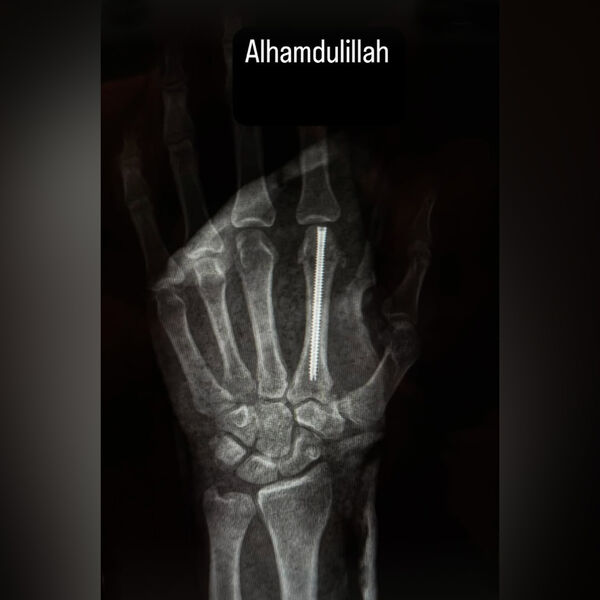

Брат Хабиба показал результат операции, где ему вставили штифт в руку

Боец Нурмагомедов вставил штифт в руку после поражения в титульном бою UFC

Российский боец Абсолютного бойцовского чемпионата (UFC) Умар Нурмагомедов на своей странице в Instagram (владелец компания Meta признана в России экстремистской и запрещена) показал результаты операции, которую был вынужден перенести из-за перелома руки, полученного в бою с чемпионом промоушена Мерабом Двалишвили.

На рентгеновском снимке можно увидеть, что Нурмагомедову вставили штифт в кисть левой руки. Боец получил перелом руки по ходу первого раунда поединка.